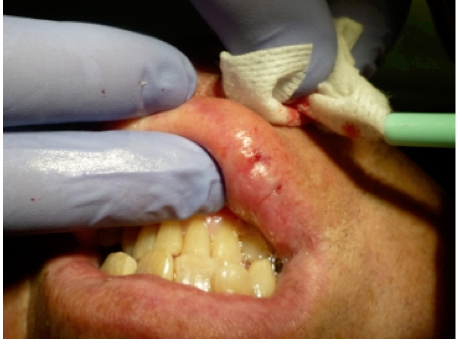

Topical anesthetic was applied to the lesion (Figure 5). Local anesthesia with 2% lidocaine with a 1:100,000 epinephrine mixture was administered by infiltration (Figure 6). Note bleeding at the injection sites in Figure 6 and Figure 7. This reminded the surgeon to be especially careful and mindful of the patient’s condition, which required anticoagulants.

Figure 6 Local anesthesia was given by infiltration. Note the bleeding in the injection sites; the surgeon had to be mindful of the patient’s history of taking blood thinners for his atrial fibrillation.

Figure 6